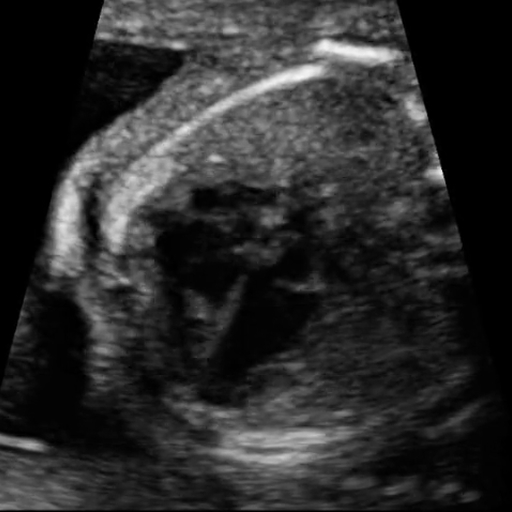

Congenital heart defect (CHD) is the most common fetal anomaly, affecting approximately 1.0% of live births, with half of those cases requiring surgical intervention [van der Linde et al.(2011)van der Linde, Konings, Slager, Witsenburg, Helbing, Takkenberg, and Roos-Hesselink, Carvalho et al.(2002)Carvalho, Mavrides, Shinebourne, Campbell, and Thilaganathan]. In such cases, early and precise screening is vital for improving outcomes [Khalil and Nicolaides(2013), Liu et al.(2019)Liu, Chen, Zühlke, Black, Choy, Li, and Keavney]. Fetal ultrasound remains the standard screening tool in clinical practice, offering accessible cardiac imaging [Yun(2011)]. However, its effectiveness relies heavily on the sonographer’s skill: even slight variations in probe angle or applied pressure can obscure key anatomical structures, potentially leading to missed or delayed diagnoses [Sharma et al.(2021)Sharma, Drukker, Chatelain, Droste, Papageorghiou, and Noble]. As illustrated in Figure 1, ultrasound suffers from common artifacts, acoustic shadowing that hides parts of the heart, speckle noise that obscures anatomical boundaries, and motion that blurs moving structures, making it challenging to locate and measure chambers consistently [Perperidis et al.(2017)Perperidis, Cusack, White, McDicken, MacGillivray, and Anderson]. These operator-dependent limitations underscore the need for automated CHD screening tools that can provide consistent and reliable analysis to assist clinicians.

(a) Acoustic shadowing

(b) Speckle noise

(c) Motion

Figure 1: Fetal four-chamber ultrasound frames showing common imaging artifacts.